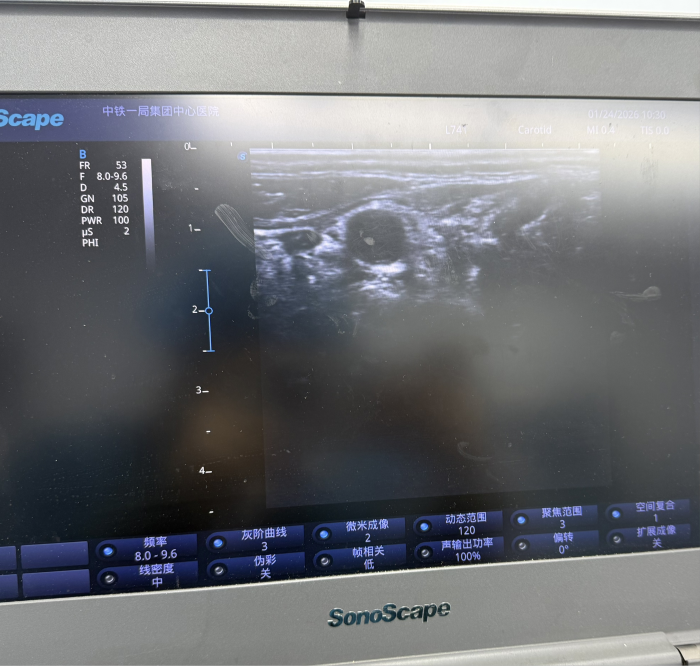

可视化操作:常规采用超声引导进行穿刺,实时显示颈部血管、神经及穿刺针位置,极大提高了操作的安全性和准确性,有效避免了传统盲穿可能引起的并发症(如血管损伤、气胸、喉返神经阻滞等)。